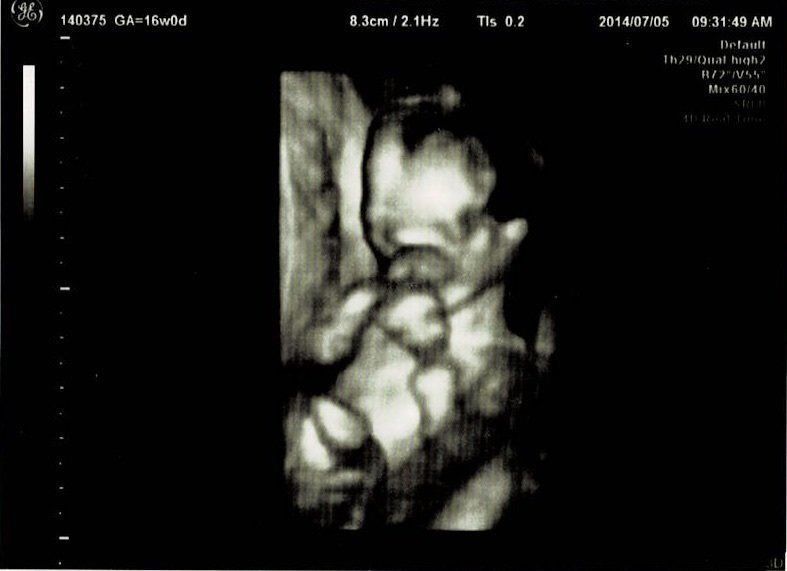

妊娠16週目エコー写真

初めての3Dエコーでした。今までレントゲンのようなエコー写真でしか赤ちゃんを見ていなかったので、芋虫みたいな見た目でも、「ちゃんと人間だ!」と不思議な気持ちになりました。エコーを見るたびに、「本当に人間ができているんだなぁ」と、毎回特別な気持ちになります。3Dエコーは、なんとなくこちらを見ている感じがして、かわいらしいと思ったり。手を口元に寄せて、すでに赤ちゃんらしい丸っこいポーズをしています。